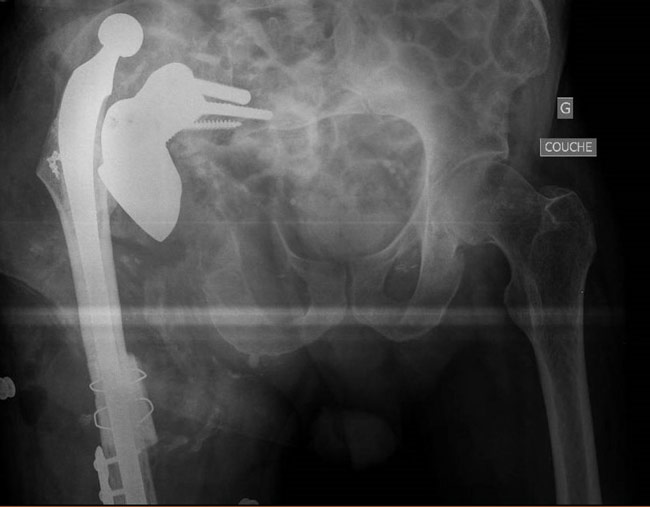

But... We noticed after removal of the drapes a massive knee instability that was not known before, and we asked for an x-ray.

A massive knee instability that was not known before

Internal fixation was impossible because there wasn’t enough bone distally. A Hinge TKR and a  bridging plate were fitted.

Internal fixation was impossible because there wasn’t enough bone distally